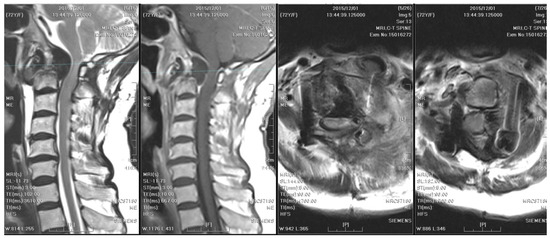

One year after surgery, an annual follow-up cervical spine MRI revealed resolution of the C1–C2 subluxation; however, fibro-osseous hypertrophy at the atlanto-odontoid joint led to mild stenosis of the spinal canal (Figure 4).

Figure 4. A follow-up cervical spine MRI taken 10 months after posterior surgery revealed resolution of the atlantoaxial subluxation; however, fibro-osseous hypertrophy at the atlanto-odontoid joint led to stenosis of the spinal canal.